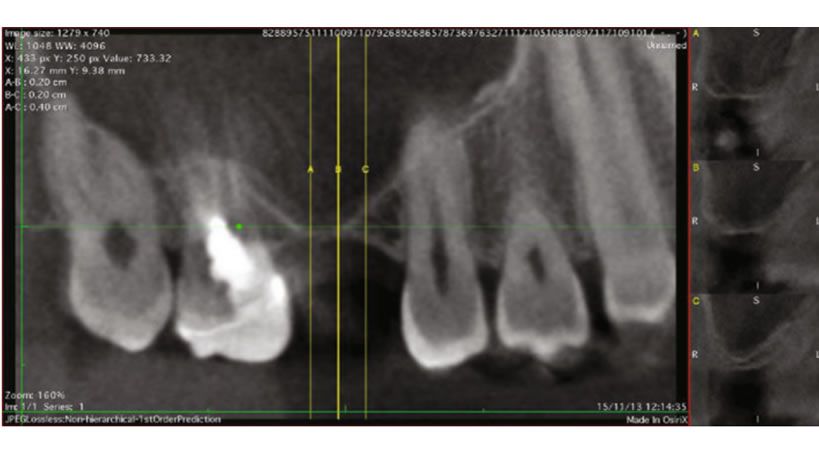

Así surgió la idea de hacer las vestibuloplastia, que es el procedimiento indicado para ganar altura en caso de colocación de prótesis. La doctora Verónica Barquero dijo que con la Javeriana se quiere hacer el estudio completo de la caracterización de esa membrana.

Acostado en la camilla, mientras le realizan la valoración y seguimiento a la cirugía, Luis cuenta que el dolor fue mínimo y la recuperación, rápida, diferente a lo que pasa en otras técnicas que dejan el hueso expuesto y la lesión abierta para que epitalice y alcance la altura. Pero este no es el caso de la membrana amniótica, explica la médica.